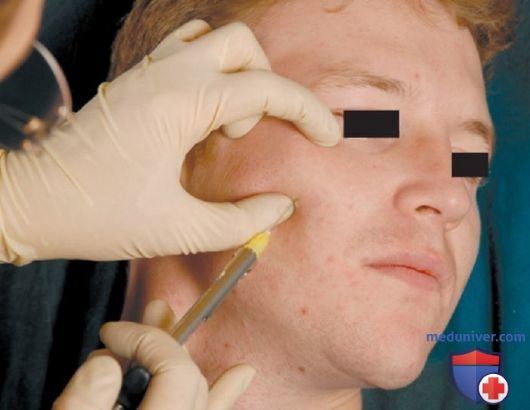

Анатомические особенности: фотографии ямок черепа, височной и подвисочной крылонебной